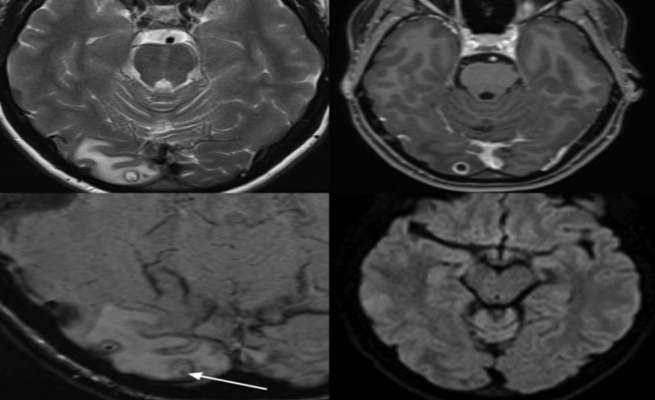

وبعد جلسة تصوير بالرنين المغناطيسي لدماغها، اعتقد الأطباء أن سبب ألمها قد يكون ناتجاً من ورم، ولكن بعد إجراء عملية لإزالته، اكتشفوا أنه في الواقع كيس مليء بيرقات دودة شريطية، وبعد إزالة الكيس، لم تحتاج المرأة إلى المزيد من العلاج.

ووفق ما ذكرت شبكة “سي إن إن”، تُعرف هذه الحالة باسم “Neurocysticercosis” (داء الكيسات المذنبة العصبي)، وهو يمكن أن يتسبب بأعراض عصبية عندما تتطور كيسات اليرقات في الدماغ.